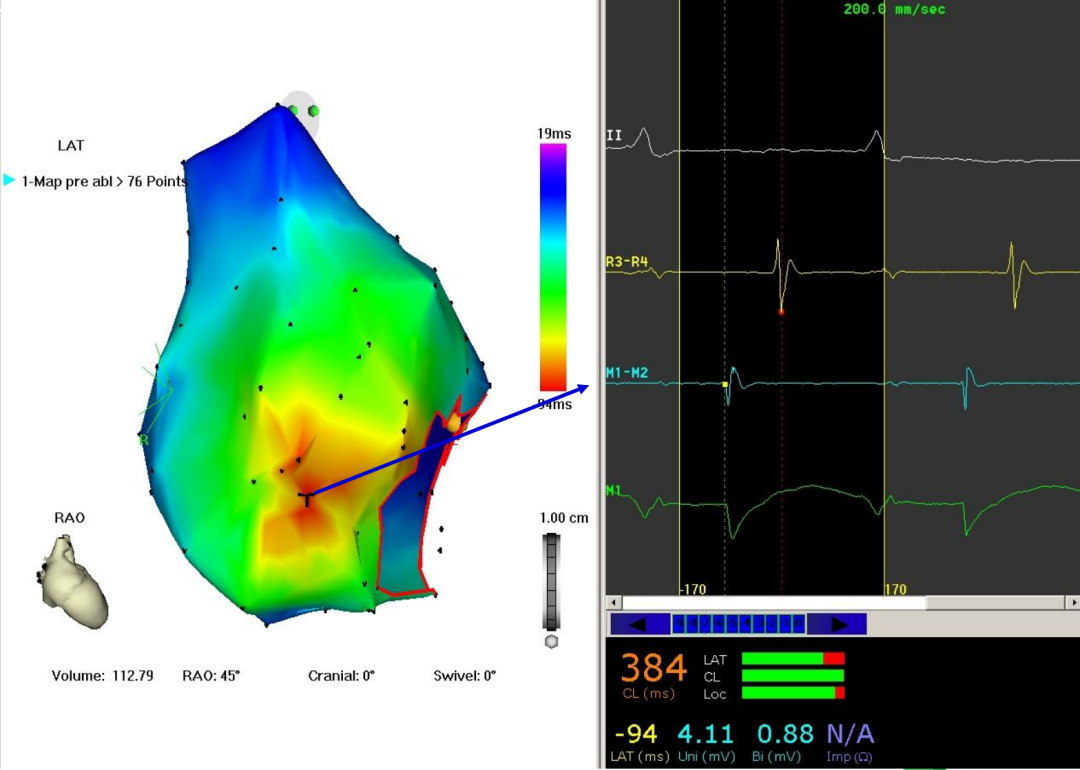

案例二

p心电图功能怎么开通异位起源P波的心电图定位_https://www.jmylbn.com_新闻资讯_第13张

p心电图功能怎么开通异位起源P波的心电图定位_https://www.jmylbn.com_新闻资讯_第14张